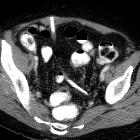

abgerissener Drainageschlauch

Fremdkörper Radiopaedia • CC-by-nc-sa 3.0 • de

Assoziationen und Differentialdiagnosen zu abgerissener Drainageschlauch: